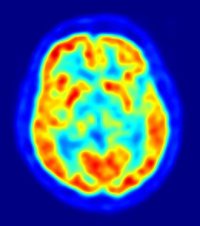

Neurona

NICOLAS P. ROUGIER/WIKIMEDIA COMMONS